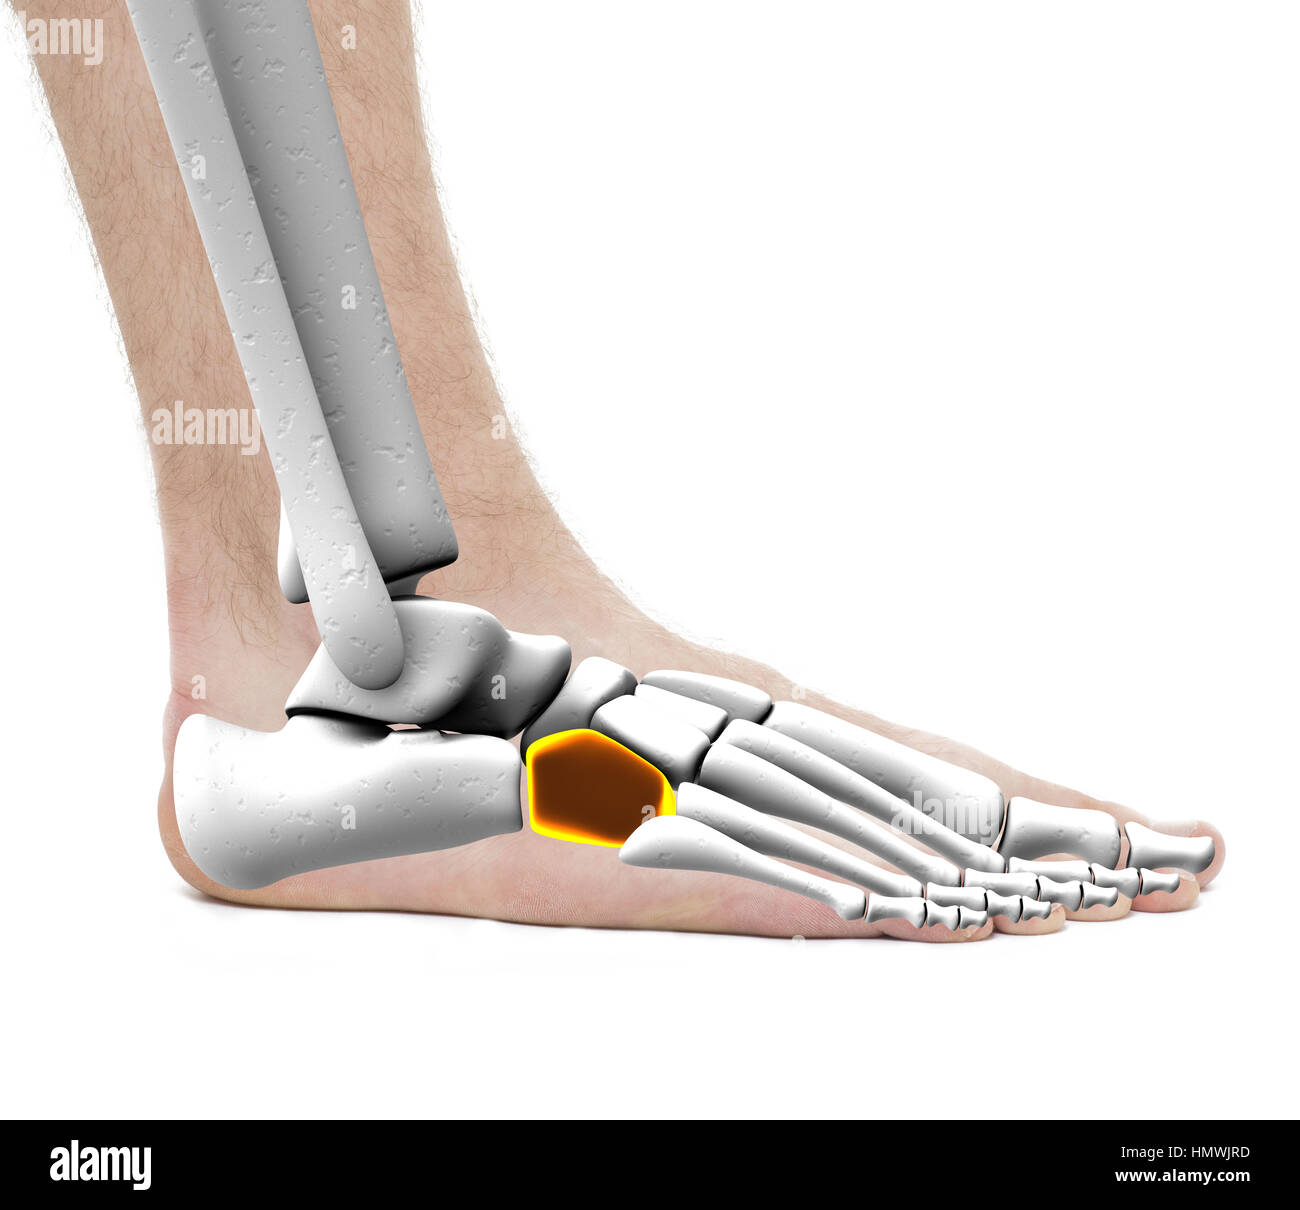

RF2R3WKY1–Illustration médicale des principales parties des os du pied en vue latérale, avec annotations.